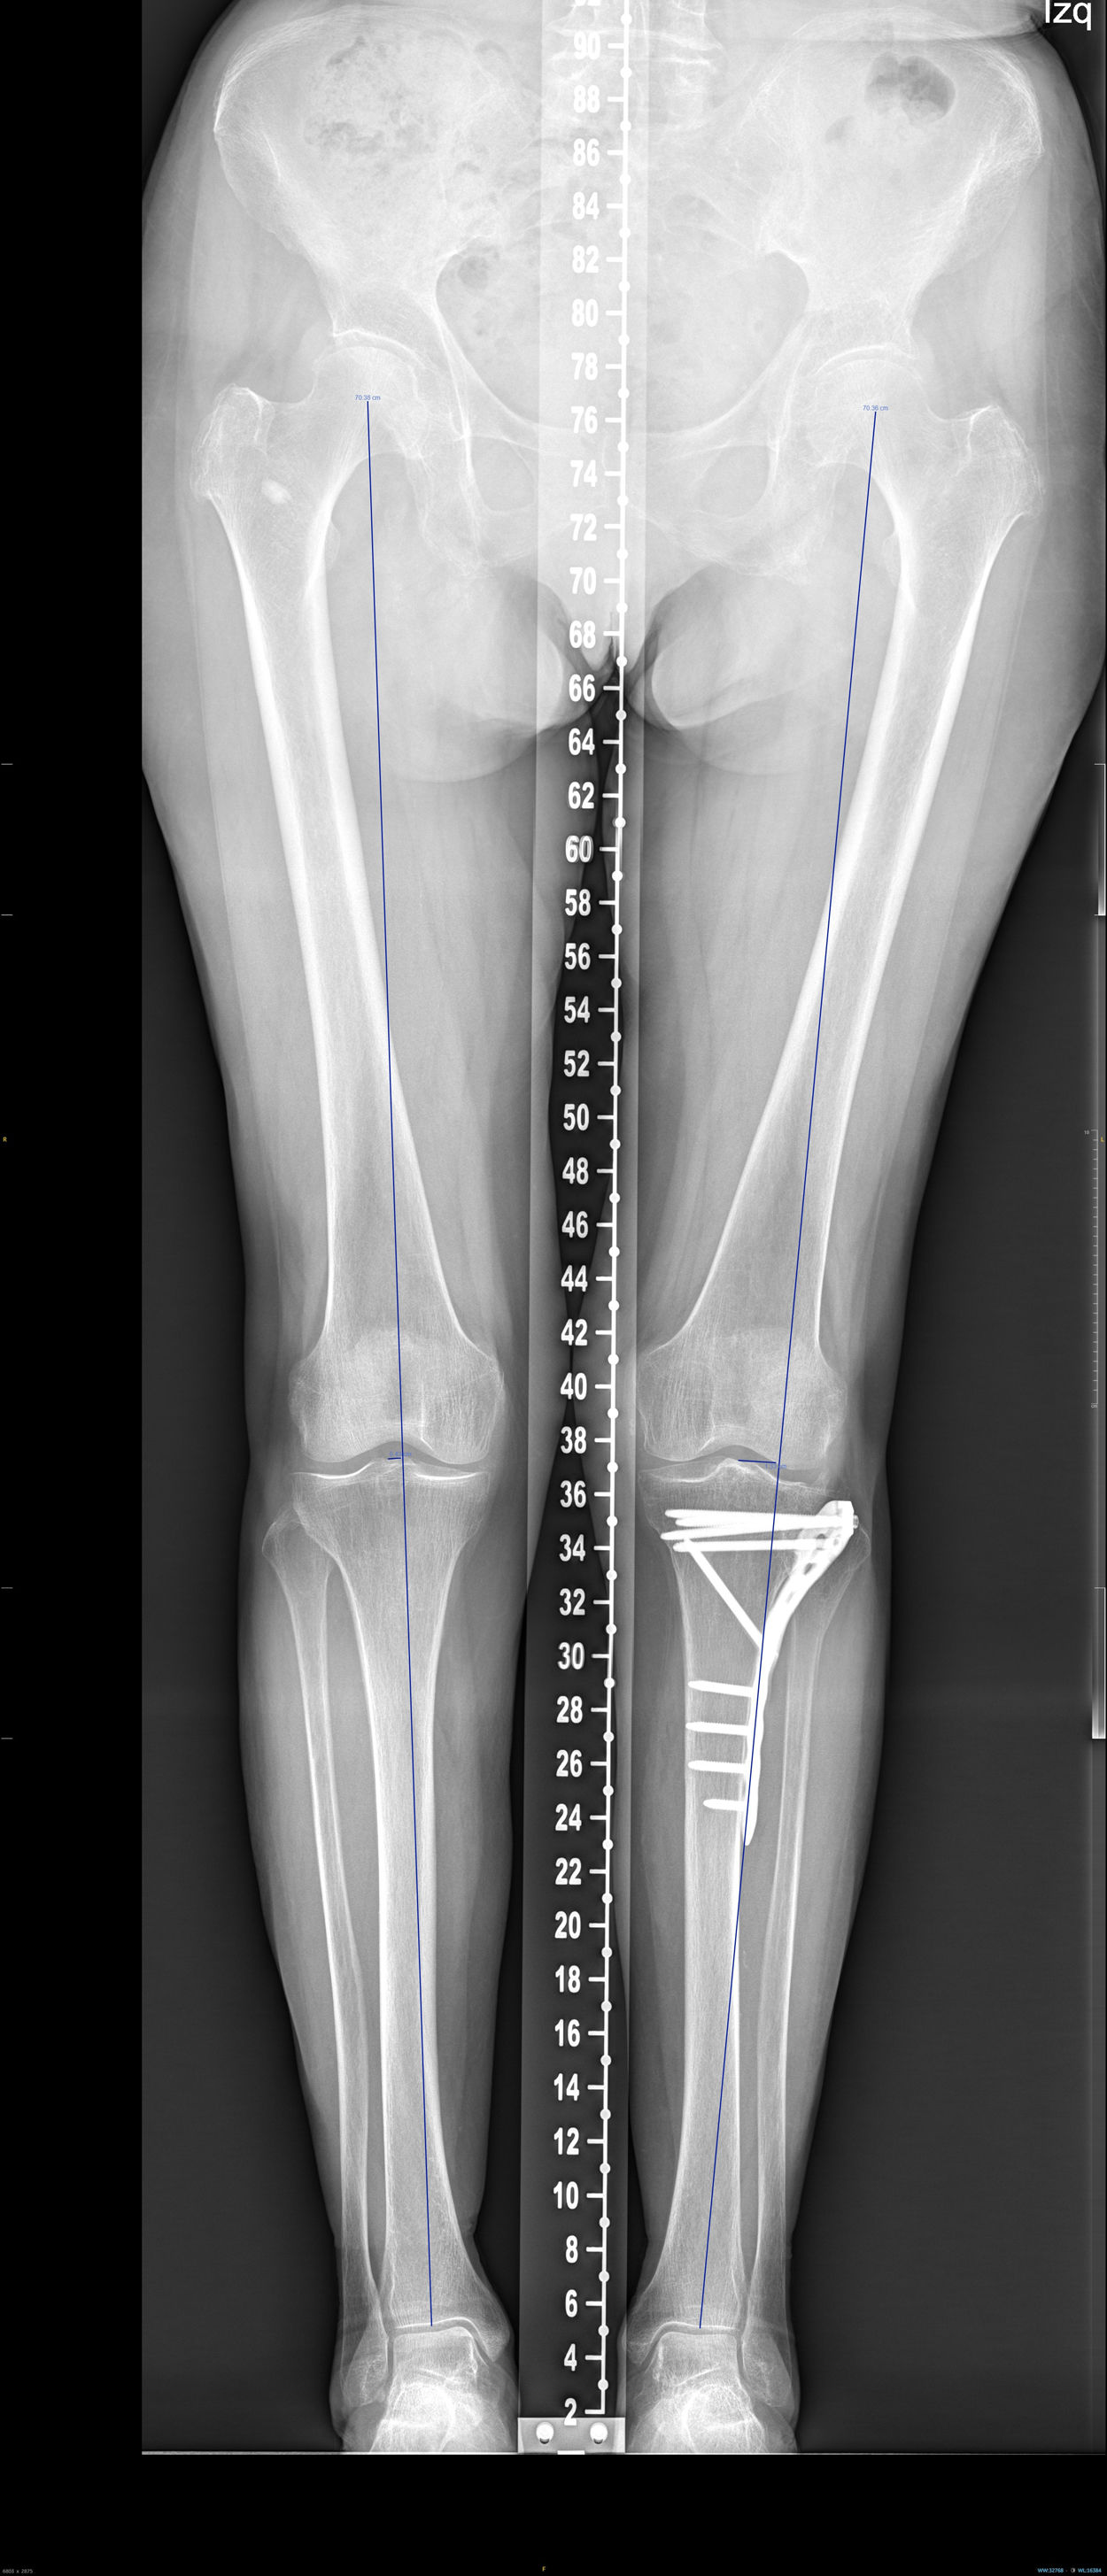

En la telemetría se analizó la desviación en mm del eje de carga respecto al miembro contralateral, el medial proximal tibial angle [MPTA) de ambos miembros y la diferencia en grados entre ellos (fig. 2).

En el análisis de la telerradiografía la diferencia de la desviación media del eje con respecto a la pierna contralateral fue de 12mm. La diferencia media del MPTA fue de −1,1grados.

| Tele Dif ejes (mm) | 12 | 11,4 | 7,5 | 16,5 | 0,2 | 44,7 |

| Dif MPTA (grados) | −1,1 | 3,2 | −2,4 | 0,2 | −8 | 8 |